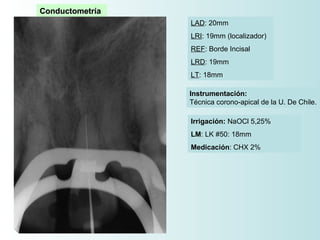

Conductometría

LAD: 20mm

LRI: 19mm (localizador)

REF: Borde Incisal

LRD: 19mm

LT: 18mm

Instrumentación:

Técnica corono-apical de la U. De Chile.

Irrigación: NaOCl 5,25%

LM: LK #50: 18mm

Medicación: CHX 2%